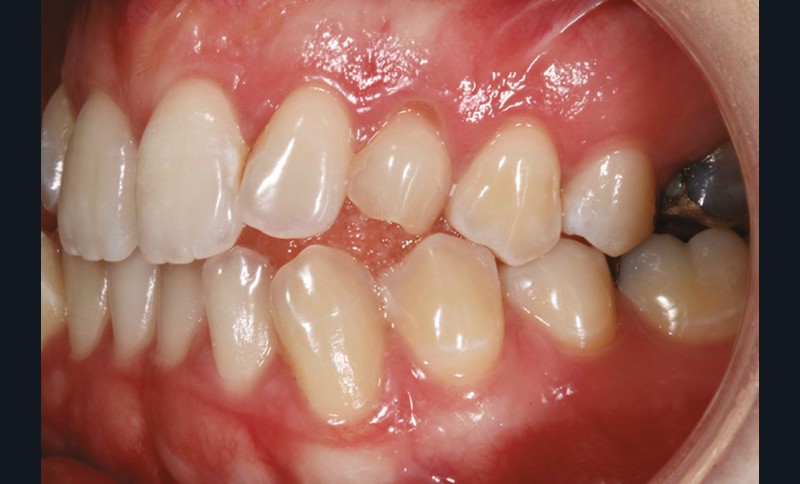

Sur le plan dentaire, on note l’absence des canines maxillaires permanentes sur l’arcade et la persistance de 63. Il existe une DDD par défaut maxillaire (indice de Bolton antérieur 90,2 %) due à l’absence des canines sur l’arcade, mais aussi à une dysharmonie de forme des dents maxillaires (fig. 2a-e).

L’examen radiologique 2D nous confirme l’inclusion de 13 et 23 en position haute, oblique en bas et en avant, couronnes en projection des apex de 11 et 21 et nous permet de quantifier le décalage squelettique (fig. 3 et 4). L‘examen radiologique 3D (cone beam) objective les rapports…